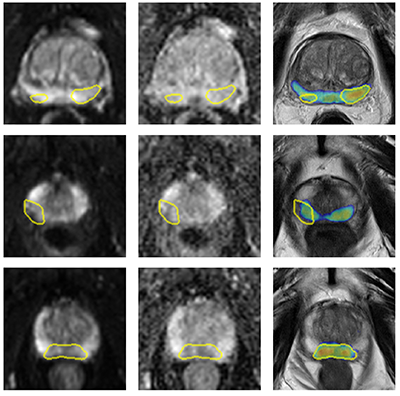

Bashkanov, O; Engelage, L; Behnel, N; Ehrlich, P; Hansen, C; Rak, M

Multimodal Data Fusion with Irregular PSA Kinetics for Automated Prostate Cancer Grading Journal Article

@article{bashkanov_multimodal_2025,

title = {Multimodal Data Fusion with Irregular PSA Kinetics for Automated Prostate Cancer Grading},

author = {O Bashkanov and L Engelage and N Behnel and P Ehrlich and C Hansen and M Rak},

year = {2025},

date = {2025-01-01},

urldate = {2025-01-01},

keywords = {},

pubstate = {published},

tppubtype = {article}